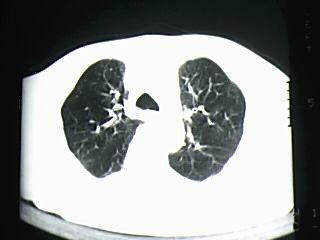

标题: CT19768:男 61岁 胸痛 咯血 一周。无发烧、无结核病史。 [打印本页]

标题: CT19768:男 61岁 胸痛 咯血 一周。无发烧、无结核病史。

考虑右肺下叶感染性病变;建议抗炎治疗后复查。

考虑右肺下叶感染性病变,建议抗炎治疗后复查。

右下肺感染性病变,建议抗炎后复查。支持